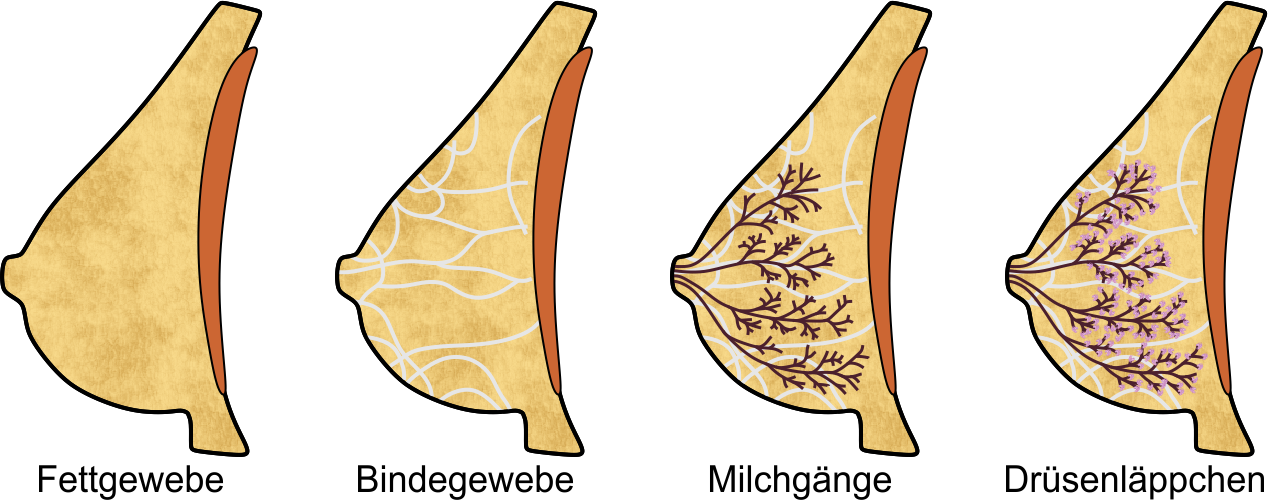

Die weibliche Brust besteht in Hauptsache aus den vier Komponenten Fettgewebe, Bindegewebe, und den Milchgängen und Milchdrüsenläppchen, die zusammen die Brustdrüse bilden:

Das Fettgewebe gibt der Brust ihre Form, das Bindegewebe durchzieht die Brust in gewölbten, fächerartigen Bahnen und verleiht ihr Stabilität. Die Milchgänge leiten die Milch zur Brustwarze, und in den Drüsenläppchen wird die Milch gebildet; die rotbraune Fläche in den obigen Abbildungen symbolisiert den Brustmuskel.